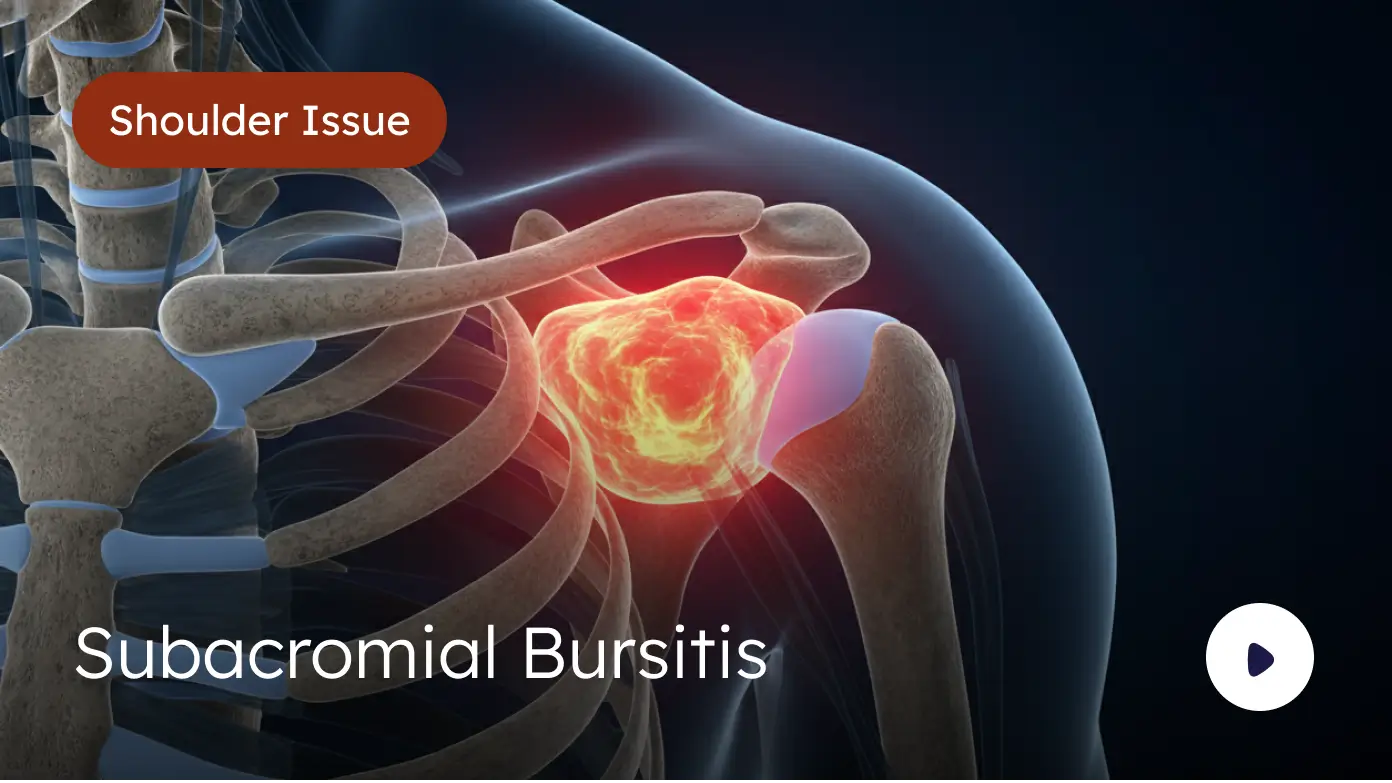

Explore Video Library

Comprehensive educational content covering orthopaedic surgery, regenerative medicine, peptide therapy, and evidence-based rehabilitation protocols.